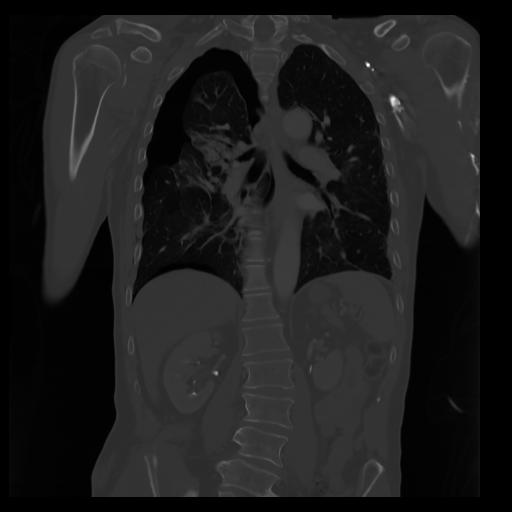

29 CUERPO,CE,Coronal,3.000,CUERPO,Coronal,